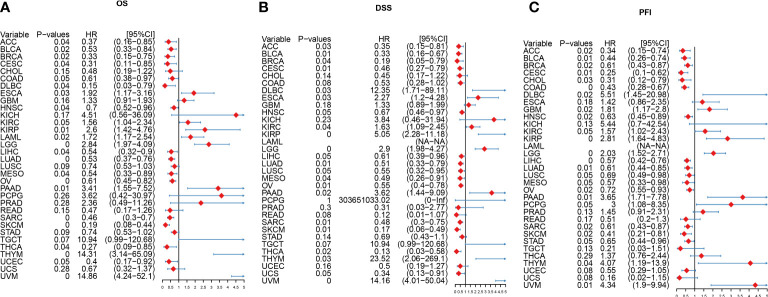

Prognostic significance of IFN-γ score in tumor

We explored the predictive significance of IFN-γ in TCGA pan-cancer. Cox Regression analysis demonstrated that IFN-γ served a protective function among patients with SKCM, SARC, OV, MESO, LUAD, LIHC, HNSC, DLBC, CESC, BRCA, BLCA, THCA, and ACC (All P< 0.05, f5). The findings from DSS analysis confirmed the protective function of IFN-γ in BRCA, THCA, SARC, MESO, OV, CESC, LUAD, SKCM, BLCA, and ACC (All P< 0.05, f5). The findings from PFI analysis illustrated the protective function of IFN-γ in BLCA, SKCM, LUAD, CESC, OV, LIHC, COAD, CHOL, BRCA, SARC, HNSC, and ACC (All P< 0.05, f5). Higher IFN-γ scores were linked to improved OS in ESCA, KIRC, LUAD, CESC, SARC, SKCM, STAD, and DLBC, as determined by KM analysis (Supplementary Figure 3). In MESO, LUSC, UCS, BRCA, OV, LUAD, CESC, HNSC, SARC, BLCA, SKCM, THCA, and ACC, higher IFN-γ expression was associated with improved OS and DSS (Supplementary Figure 4). Additionally, a longer PFI was associated with higher IFN-γ scores in OV, BLCA, STAD, HNSC, SKCM, CESC, LUSC, CHOL, LUAD, MESO, BRCA, COAD, LIHC, AD, and ACC (Supplementary Figure 5). From these findings, the IFN-γ score could improve the predictive significance of classical prognostic markers. Moreover, IFN-γ is strongly linked to the prognosis of many types of malignancies, suggesting that it may have a beneficial influence on the prognosis of patients with these tumors. In addition, we performed GSEA analysis of immune activation genes, immune suppression genes, immune checkpoints, chemokines, chemokine receptor gene sets and compared the variability between cancer and para-cancer (Supplementary Figures 6A–E). The results showed that the above gene set scores were either high or low in the tumors and lacked results similar to the consistency of IFN-γ-related genes. In addition, we performed 20 random samples of 10 genes each time for the above gene sets to obtain 20 random immune gene sets and perform GSEA analysis. The results were similar to previous results in that no gene sets were observed to have a consistent up- or down-regulation trend across tumors (Supplementary Figure 6F). The above results suggest that the expression status of IFN-γ-related genes in tumors is regulated by the biology behind it, and is not a coincidental result that can be obtained by an arbitrary set of immune genes.